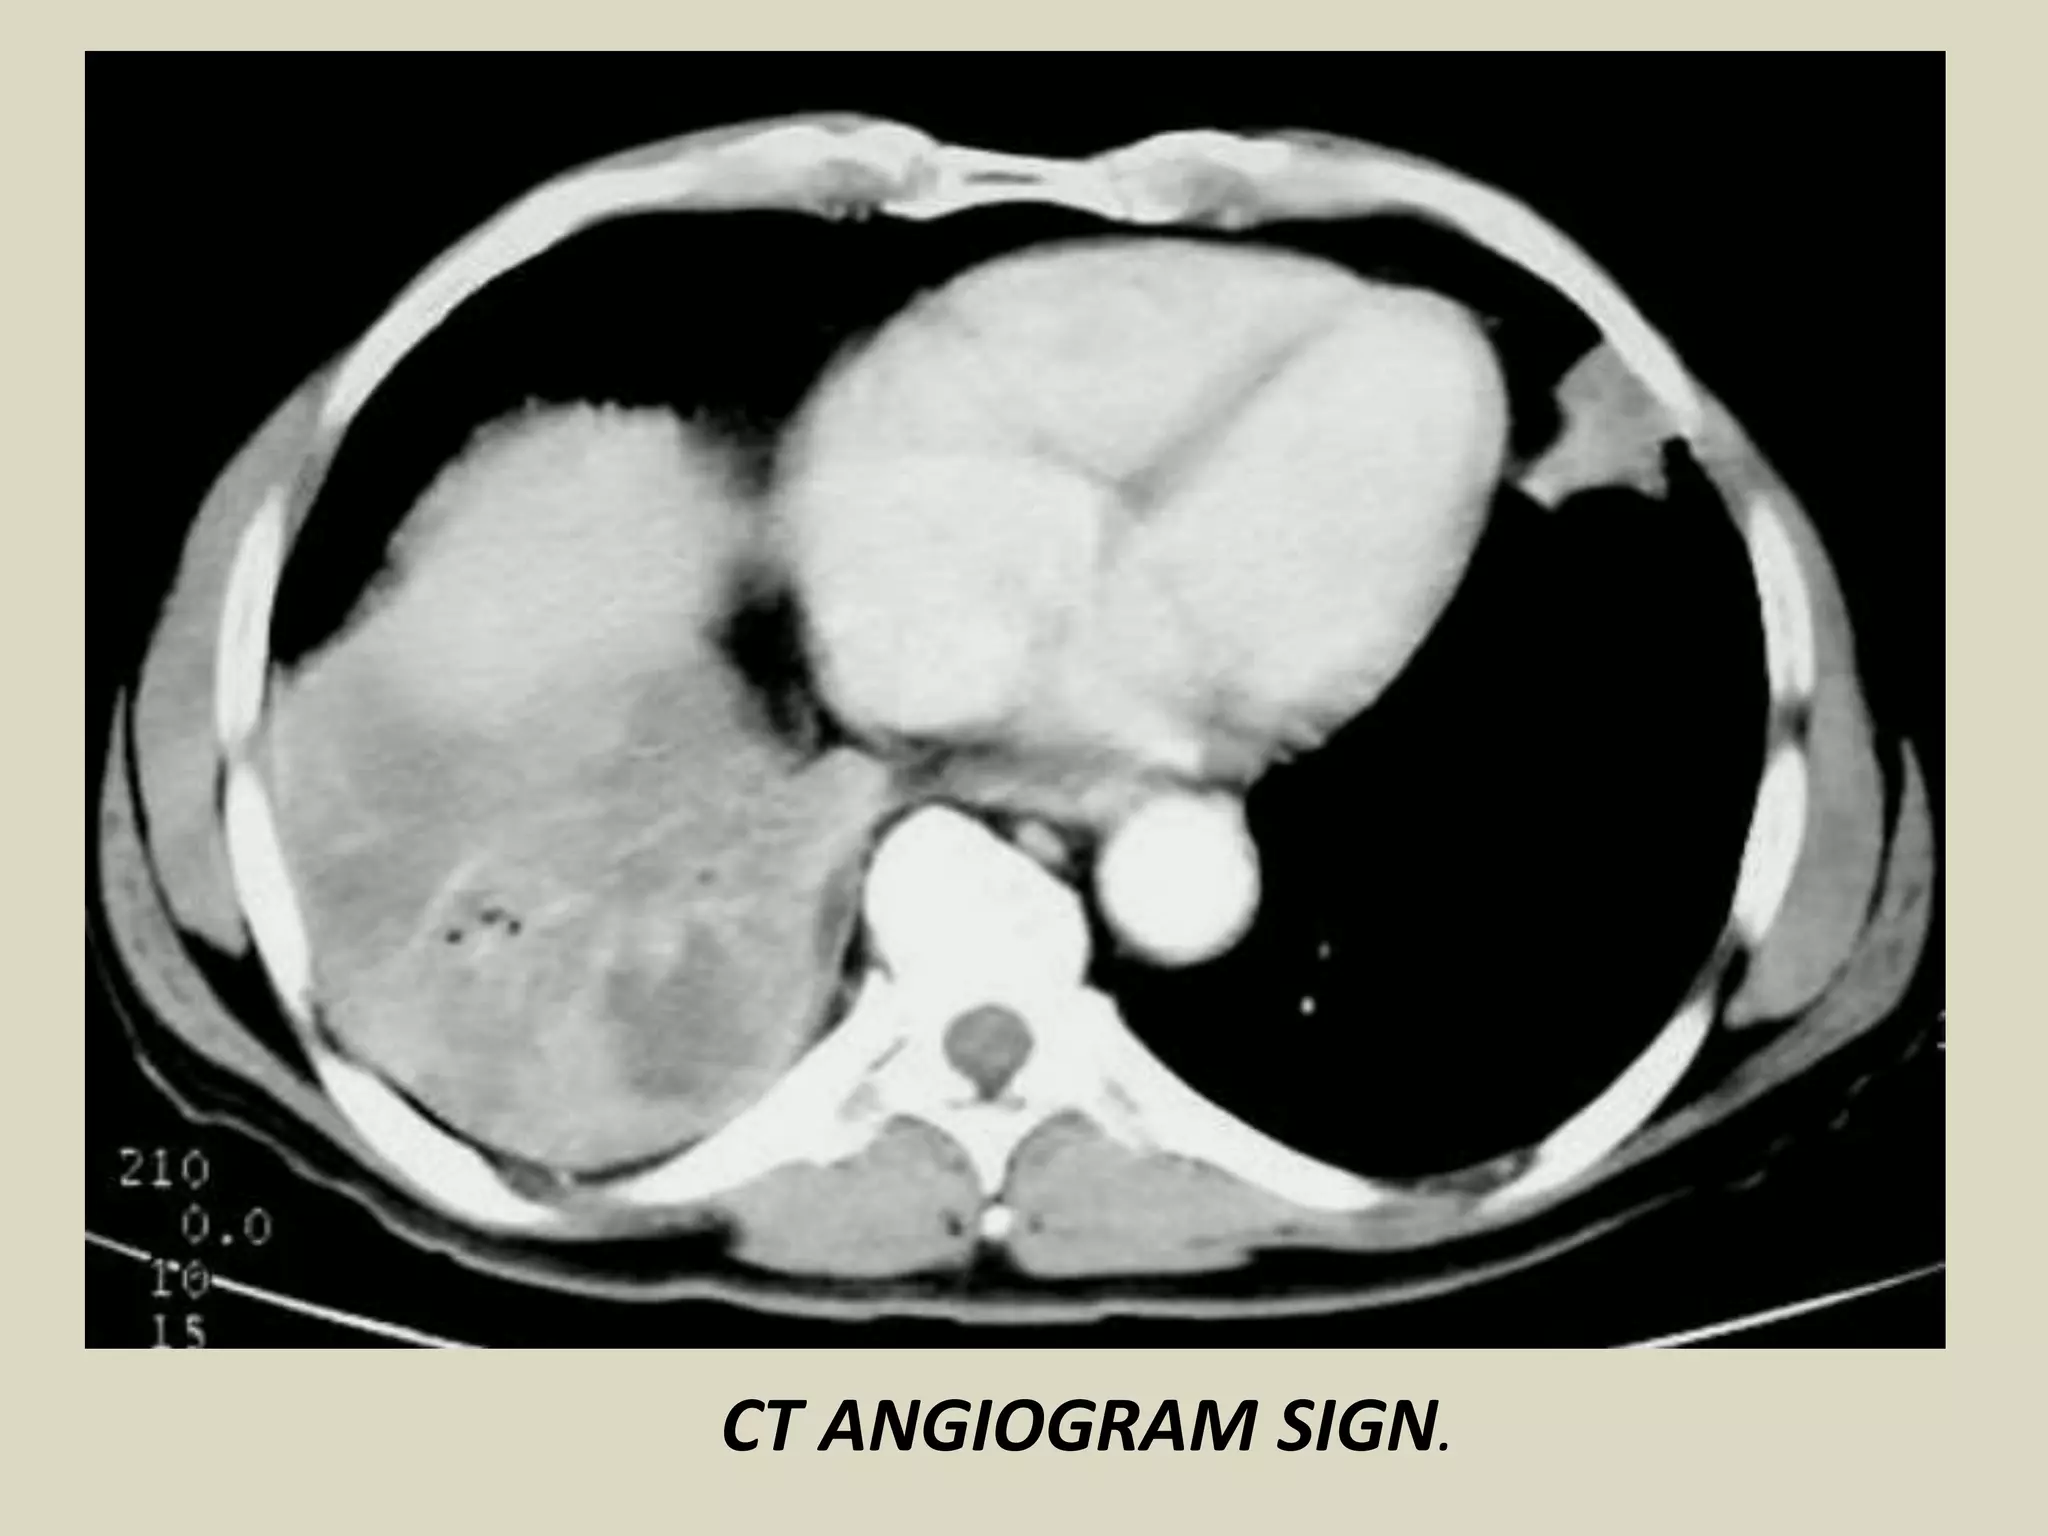

CT ANGIOGRAM SIGN

Finding may be seen on CT of chest after IV contrast material

administration.

Consists of enhancing branching pulmonary vessels in

homogeneous low-attenuating consolidation.

Low-attenuating component can be caused by production of

mucin within air spaces

Initially described in 1990 by Im et al as a specific sign (92%)

of lobar bronchoalveolar carcinoma

Also seen in:

- pneumonia

- pulmonary edema

- obstructive pneumonitis central tumor

- metastasis from GI carcinomas

- lymphoma

CT ANGIOGRAM SIGN. Chest CT and schematic drawing.

CT ANGIOGRAM SIGN.